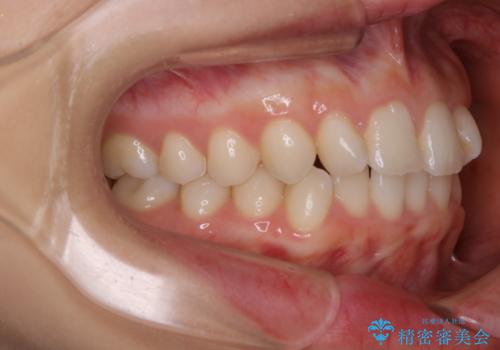

動きづらい前歯のねじれもマウスピース(インビザライン)で改善

- 前から2番目の歯が捻じれていることが気になるとご相談にいらした方です。

インビザラインFULLで治療を行いました。

上の前から2番目の歯は、一般的に周囲の歯と比べて小さく、動きづらい歯であると言われています。前歯にゴムかけを行うことで理想的な位置まで歯を動かしてくることが出来ました。